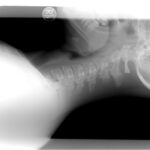

The initial diagnostic assessment of a suspected distal radius fracture begins with plain radiographs of the wrist, including anteroposterior (AP) and true lateral views. These images are used to evaluate fracture lines, displacement, angulation, comminution, and articular involvement. Radiographs also allow for preliminary classification of the fracture pattern.

The Frykman classification can be applied to plain films to identify whether the fracture involves the radiocarpal and/or distal radioulnar joints, and whether an ulnar styloid fracture is present.

The AO/OTA classification system provides a more comprehensive morphological description, categorizing fractures into:

- Type A: Extra-articular fractures (no joint surface involvement)

- Type B: Partial articular fractures (a portion of the joint remains attached to the shaft)

- Type C: Complete articular fractures with metaphyseal comminution and separation of the articular surface from the shaft.

This systematic classification assists in determining fracture complexity, instability, and the need for operative intervention.

In cases where the fracture pattern is complex or intra-articular, computed tomography (CT) is recommended to delineate fragment configuration, articular step-off, and metaphyseal comminution. CT-based reconstructions are particularly useful for accurate AO subclassification and surgical planning. Magnetic resonance imaging (MRI) may be reserved for suspected soft-tissue injuries, such as ligament tears or occult fractures not visible on radiographs.

Careful attention to radiographic alignment parameters, such as radial height, inclination, volar tilt, and ulnar variance, supports accurate classification, guides treatment planning, and helps predict functional outcomes.